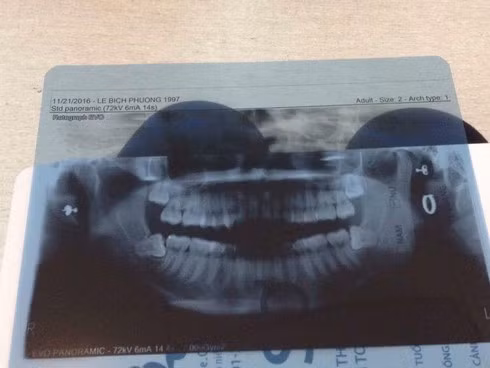

Không phải cứ khi trưởng thành bạn sẽ có răng khôn mà ước tính có khoảng 35% dân số sẽ không mọc răng khôn. Thường thì mỗi người thường có bốn răng khôn ở bốn góc hàm. Vậy câu hỏi đặt ra là với những người này răng khôn nằm ở đâu.

Thực chất lúc này răng khôn sẽ “ngoan ngoãn” nằm dưới xương hàm bình yên đến hết đời.